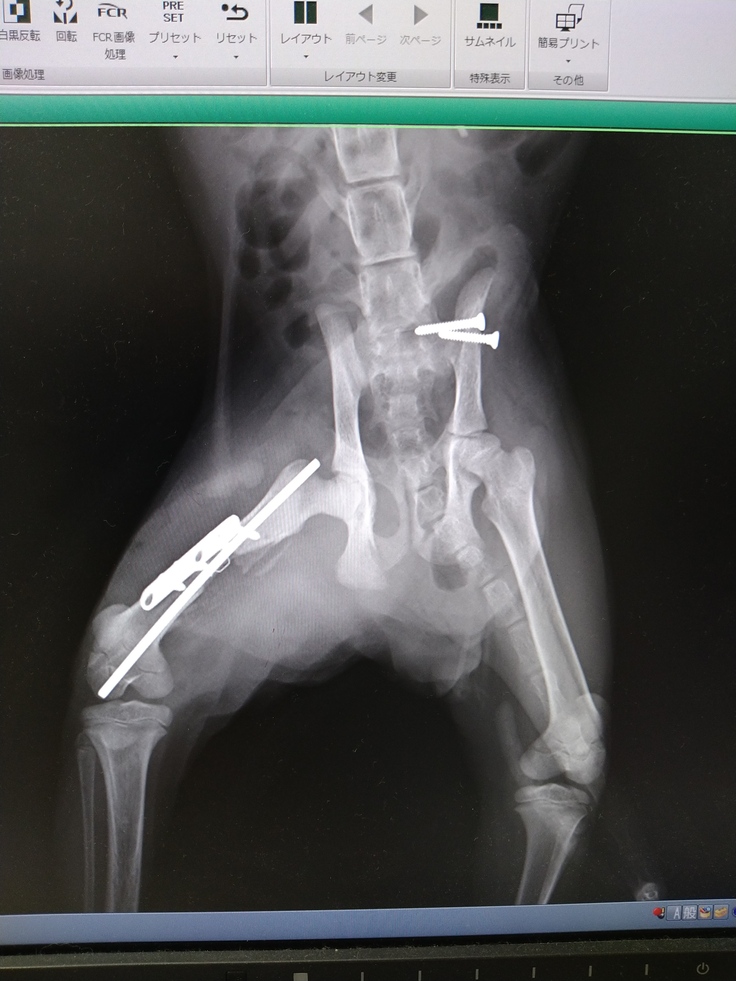

いつもお世話になっている動物病院に連れていき、診察していただいた結果は「骨盤と大腿骨の骨折」。

性別はオスで、生後4ヶ月ぐらいだそうです。

現在は骨折の手術を終え、順調に回復しています。